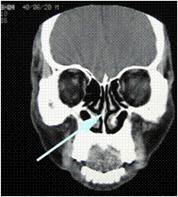

彎曲した鼻中隔(黄色い矢印)と粘膜の肥厚した肥厚性鼻炎(※)